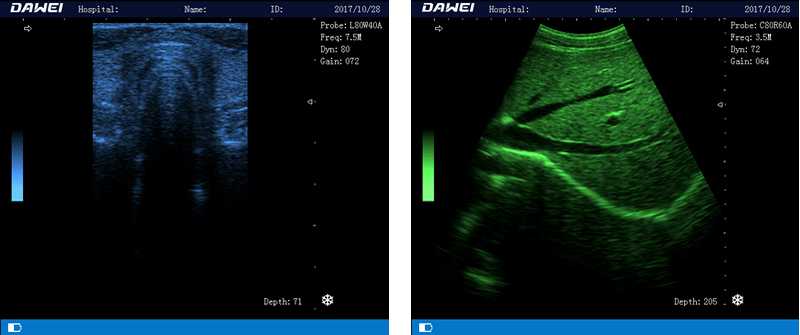

筆記本全數(shù)字超聲診斷儀

1.優(yōu)質(zhì)的數(shù)字成像技術(shù),圖像更清晰

5.體積小巧,圖像清晰,操作方便,續(xù)航能力強